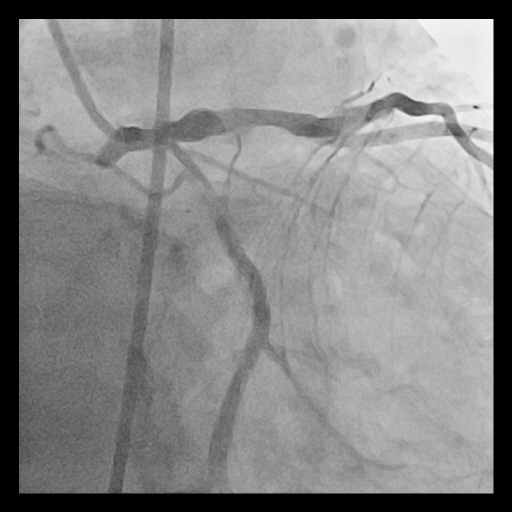

A 73-year-old man with diabetes, hypertension, dyslipidemia, and a history of smoking presented with ongoing chest pain. He was referred after emergent angiography at an outside hospital revealed a severely calcified left main bifurcation disease with subtotal proximal LCx stenosis (Medina 1,1,1) and a SYNTAX score of 27.

Relevant Catheterization Findings

Coronary angiography showed long, tram-track dense calcification involving the left main bifurcation with subtotal occlusion of proximal LCx and diffuse proximal LAD disease. The calcified plaque exhibited significant radiopacities visible before contrast injection, suggesting a deep concentric calcium burden.